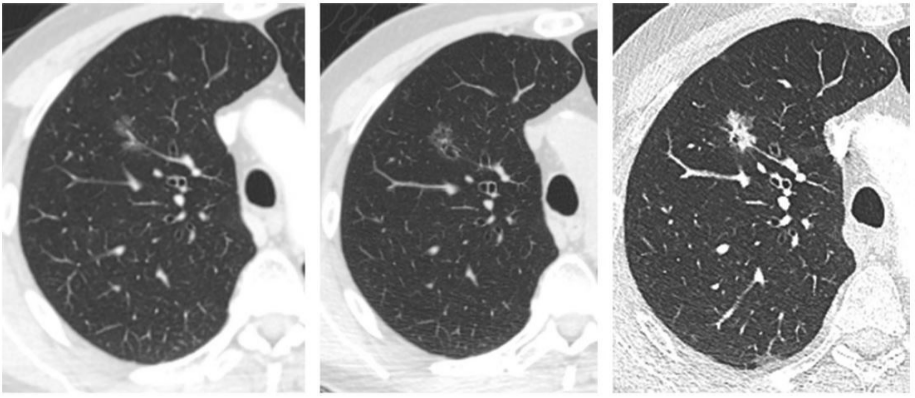

图片

什么是肺部结节

根据国内外肺部结节诊治指南与共识:肺部结节按数量分为单发肺结节和多发肺结节;按密度分为实性结节、部分磨玻璃结节和纯磨玻璃结节;按大小分为肺结节(≤30mm)、肺小结节(≤10mm)和肺微小结节(≤5mm) 。

肺部结节的病因有良性和恶性之分。

其中良性病因包括:(1)良性肿瘤(2)感染或炎性病变(3)血管性病变(4)其他(肺内淋巴结、肺不张、支气管囊肿、黏液嵌塞等)。

恶性病变包括:(1)原发性肺肿瘤 (2)转移性恶性肿瘤。

肺部结节是指直径≤3cm的长在肺实质内的结节状阴影,它可以为单独一个,也可以是多个。

❖肺肿物:直径>3cm;

❖肺结节:1cm<直径≤3cm;

❖肺小结节:5mm<直径<1cm;

❖肺微小结节:直径<5mm。

肺内很多疾病都会形成结节,借助CT影像学,通过观察结节的特征,并结合病史可帮助判断结节是良性还是恶性。大部分结节是良性的,但也不排除转化为恶性的可能,恶性结节会有一定比例演变为早期肺癌。